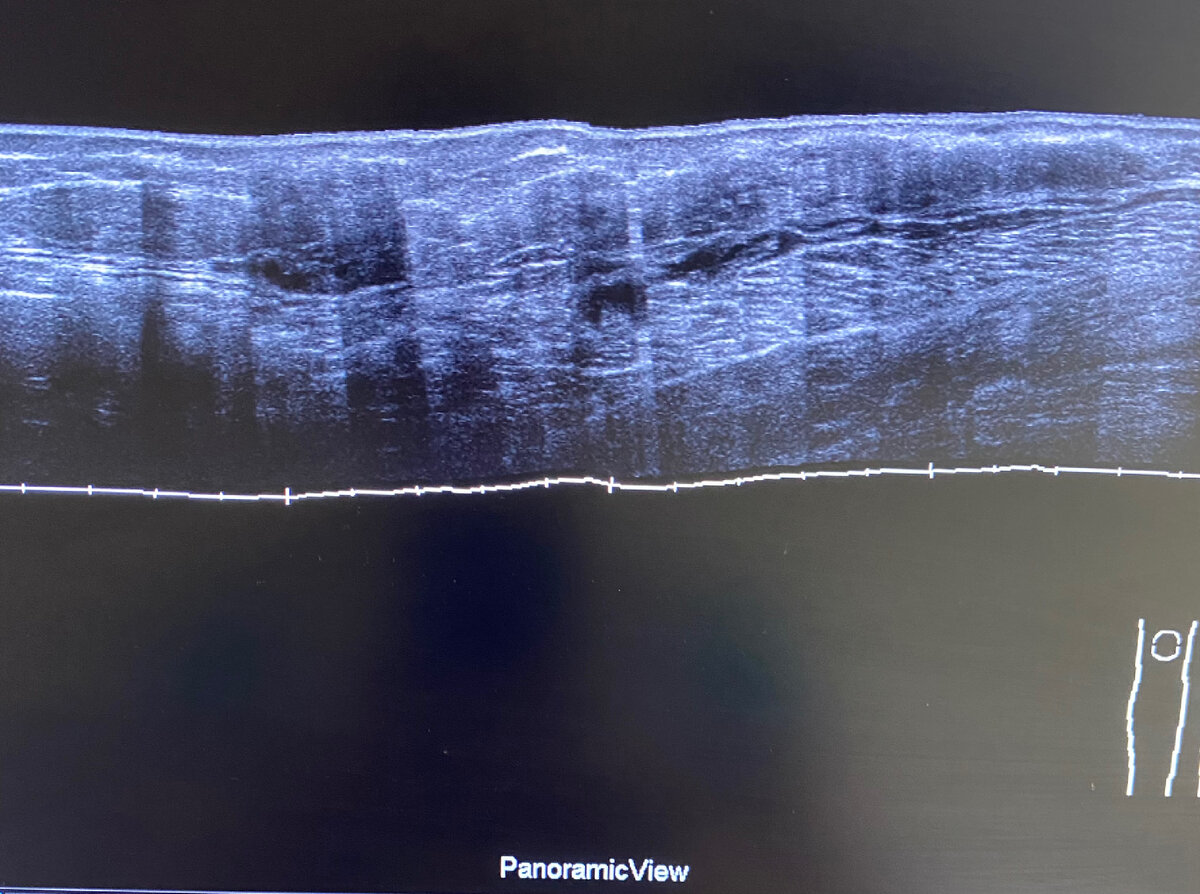

Представляю вам случай наличия безоболочечного геля  в мягких тканях бедер и голеней с обеих сторон. Посмотрите как по разному могут выглядеть скопления ПААГ в зависимости от места введения и реакции тканей. В данном случае гель локализуется внутримышечно, в подкожно-жировой клетчатке в виде гелеом, а также в ПЖК в виде диффузного распространение геля и фиброзных изменений ткани (нет четкой дифференцировки кожи и гиподермы). В одном случае есть гелеома с воспалением. Хорошую визуализацию распространённости геля для лечащего врача дают панорамные снимки.